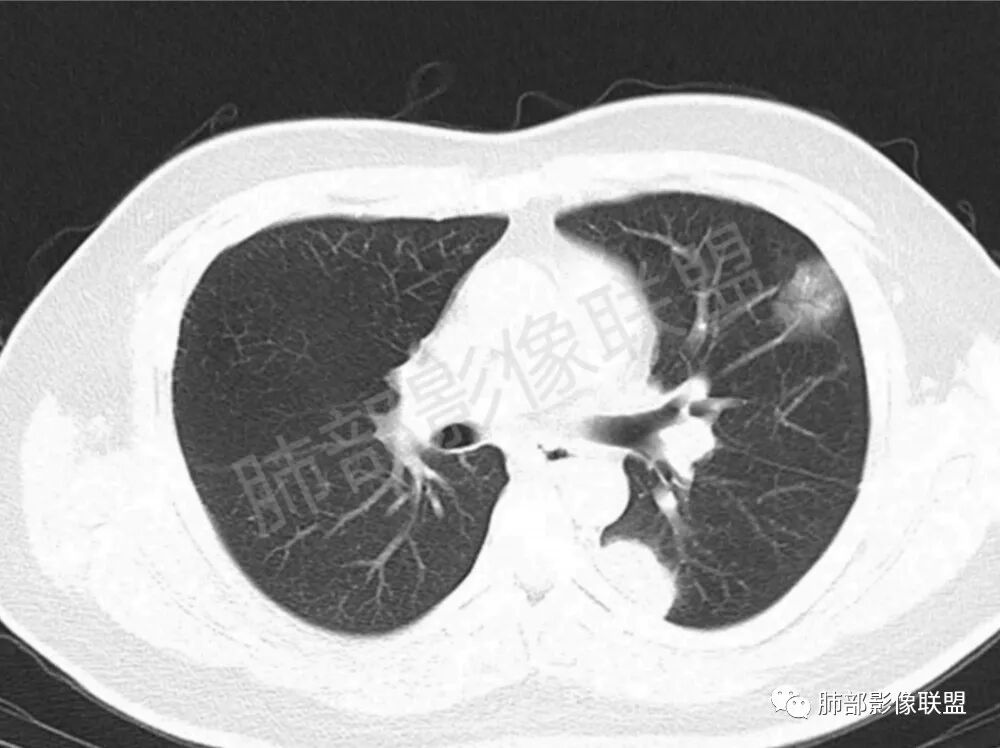

男性,22岁,HIV病史,症状半年,双肺多发大小不等结节影,边缘光滑,密度均匀,以胸膜下分布为主,部分与胸膜相连,胸膜下脂肪间隙可见,病灶近段支气管走行病灶内,远端似有堵塞,无增强图像,考虑隐球菌,鉴别:淋巴瘤,GPA

双肺多发结节影,膨隆,边缘光滑,圆顿,沿支气管血管束分布为主,部分贴胸膜,部分见空洞,空气支气管征

男,22,半年前咳嗽伴少痰,查HIV阳性,痰查TB阳性,既往有肺部斑片影伴空洞、纵隔淋巴结肿大、脾大。SCC、CA50、CA199、FER增高,此次胸部CT:两肺多发结节影,部分沿血管束分布,部分贴胸膜下,大小不一,密度不一,部分较散、边缘模糊,部分较实、圆钝、周围模糊晕,部分结节有支气管进入穿行自然,部分结节有血管分支自如通过。考虑HI∨相关淋巴增殖类病变,淋巴瘤?LYG?鉴别PC、TB。

青年男性,半年前咳嗽,HIV阳性,结核DNA阳性,肿标糖类抗原和铁蛋白增高。外院影像有纵隔淋巴结增大伴脾大,肺部病灶空洞。现在影像:肺内多发沿支气管分布(有支气管充气征,长轴沿支气管分布)及胸膜下分布(平行于胸膜)的大小不等结节,个别伴有空洞,双侧腋窝淋巴结肿大。纵隔图片不够,是否还有淋巴结肿大未知,脾脏未显示。

1.双肺多发大小不一结节,外围为主,边界尚清,部分周围似有GGO

2.类圆形,部分与胸膜相连,糊墙

3.支气管通畅或近端堵塞

影像学缺乏特征性,以支气管血管周围、胸膜下及双肺下叶周边多发结节影最多见,结节易坏死形成空洞,伴有游走性和多变性的特征,结节周围可有磨玻璃样晕征,有时也可见单发结节影、薄壁的囊状阴影或弥漫性浸润影。肺门、纵隔淋巴结肿大少见, 可见胸腔积液和气胸。

结节型∶表现为两肺多发大小不等的结节,以两肺中下野多见,结节边缘欠锐利;